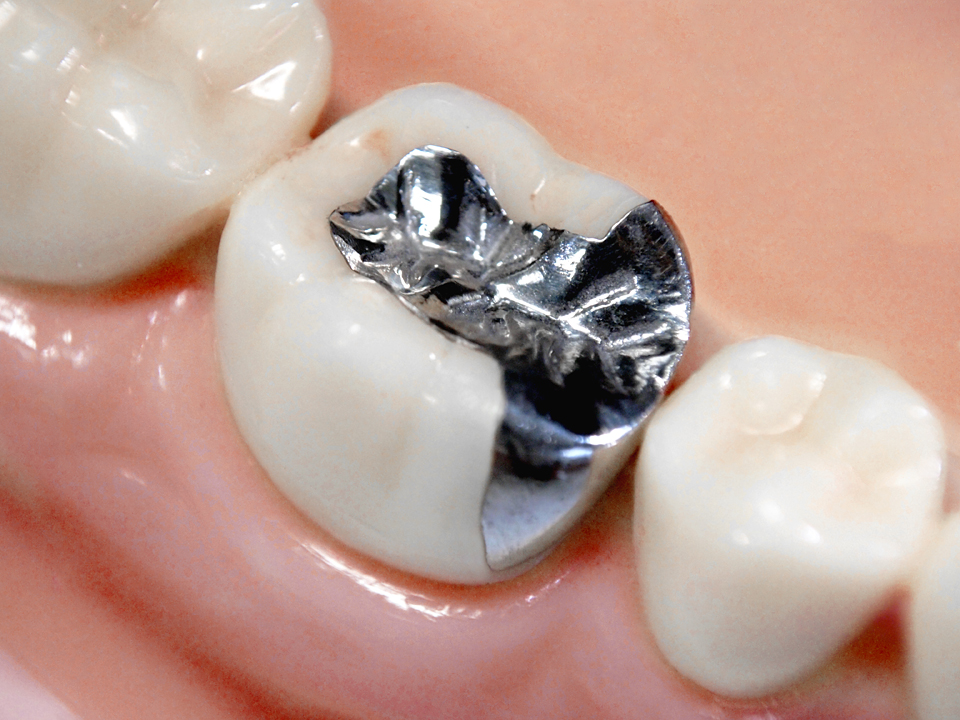

お口にこんな金属が

入っている可能があります

アマルガム

詰め物に使われてきたアマルガムは、水銀を50パーセント含んだ合金です。口の中で水銀が溶け出し体内に蓄積され、金属アレルギーの症状を引き起こすことがあります。